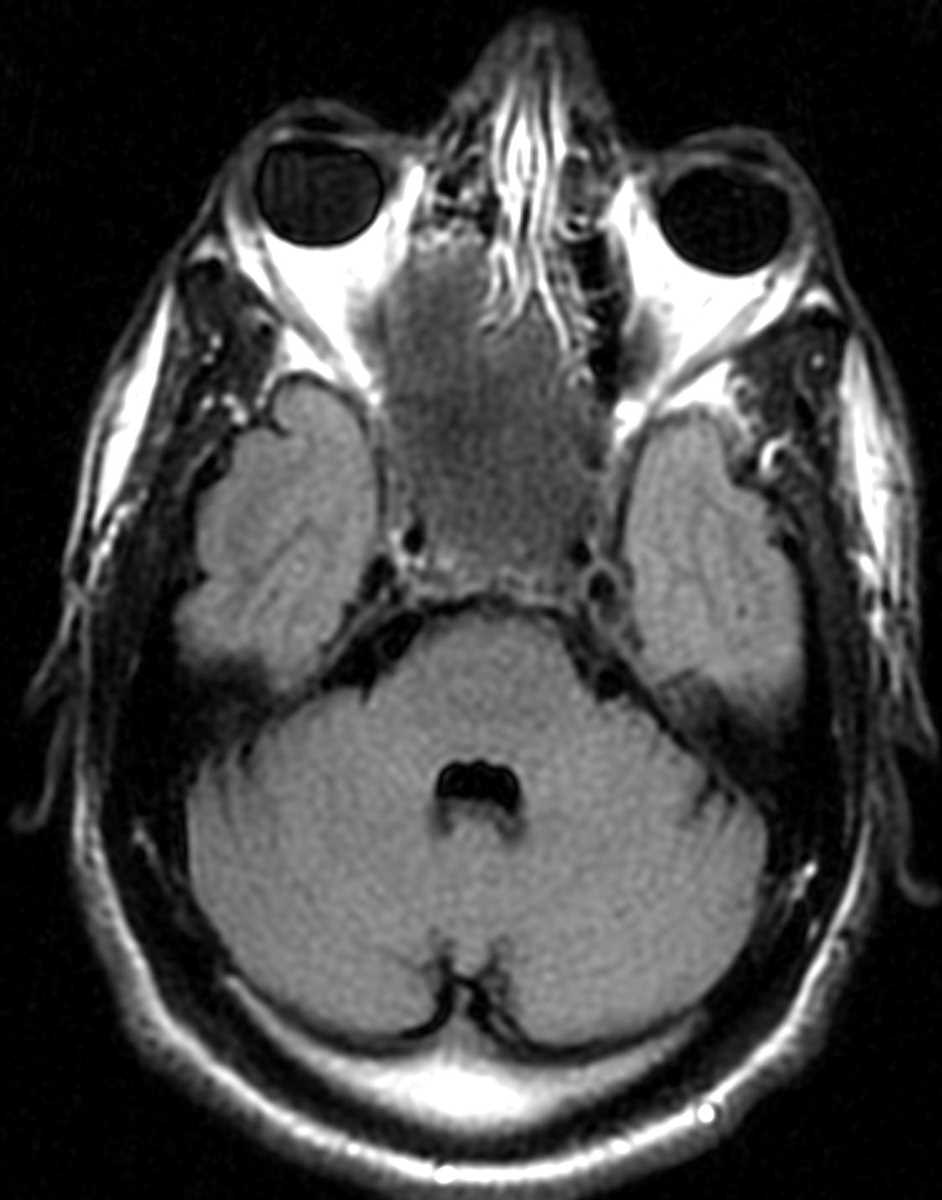

Metastases- spine, thyroid

A large, expansile mass infiltrates the posterior elements of the C2 vertebral body with mild concentric encroachment of the spinal canal. This was proven histopathologically to represent a site of follicular thyroid carcinoma metastatic disease. Thyroid and renal cell carcinoma are classic causes of "exploding" lytic osseous lesions.